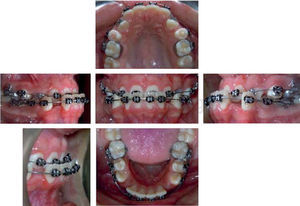

The patient shows a mesocephalic facial biotype, her lower facial third is slightly decreased and her ear pavilions have an asymmetric projection. Her mouth width matches her inter-iris distance, she has lip competence, thick lips, a straight nasal septum, a slightly concave profile, a normal cervico-mental distance, the aesthetic line within acceptable range, a slightly everted lower lip in front of the aesthetic facial line, lip competence and good development malar (Figure 1).

In the intraoral analysis, she had a deep anterior crossbite, her lower midline was diverted with respect to the upper 2mm to the left, she presented a 5mm overbite and a 3mm overjet, class I molar relationship, indeterminate bilateral canine class, ovoid upper arch form, absence of the permanent and temporary canines (significant loss of arc length), lower dental arch ovoid, crowding and 3mm mild curve of spee (Figure 2).